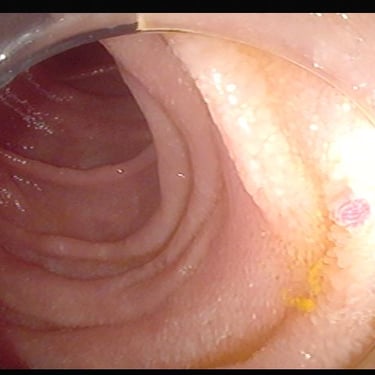

Colonoscopia

Telangiectasias intestinales